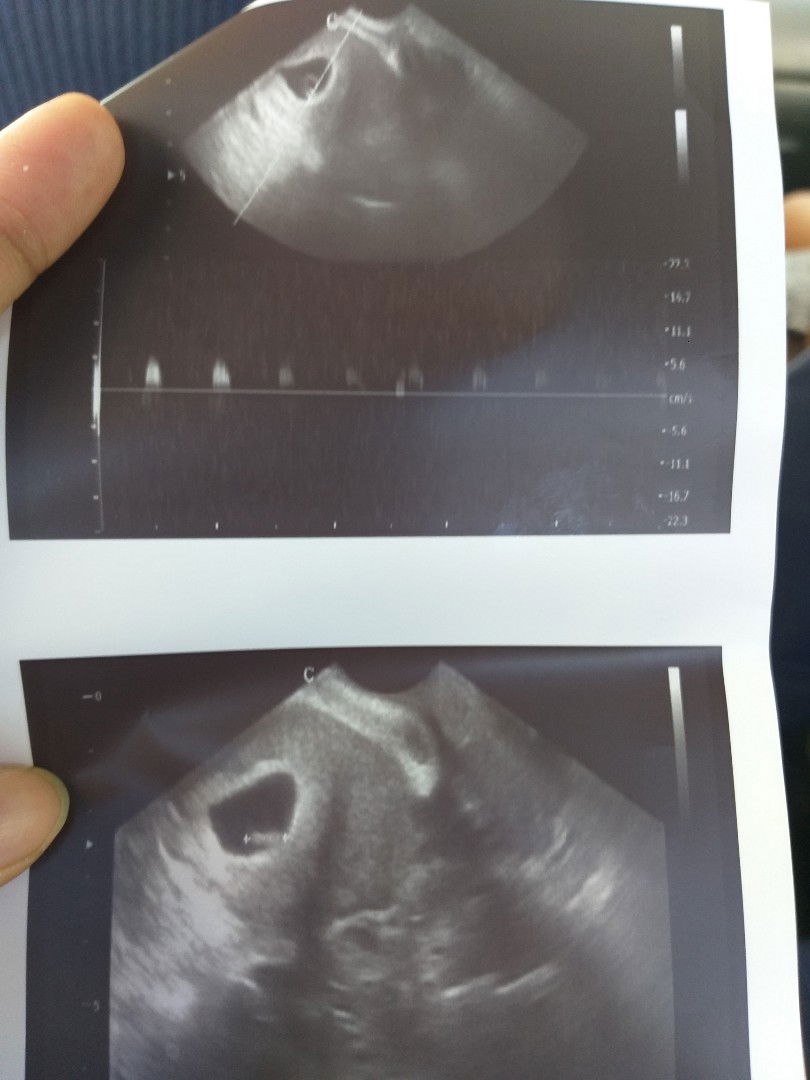

Super Happy. 🥰🥰🥰 Yung last year nagmiscarriage ako hindi nagkaheartbeat si baby, sa dating ob pa din ako.. ung assistant at si doktora Super happy din sa naging result.. may heartbeat na si baby ko. 🥰🙏🙏🙏